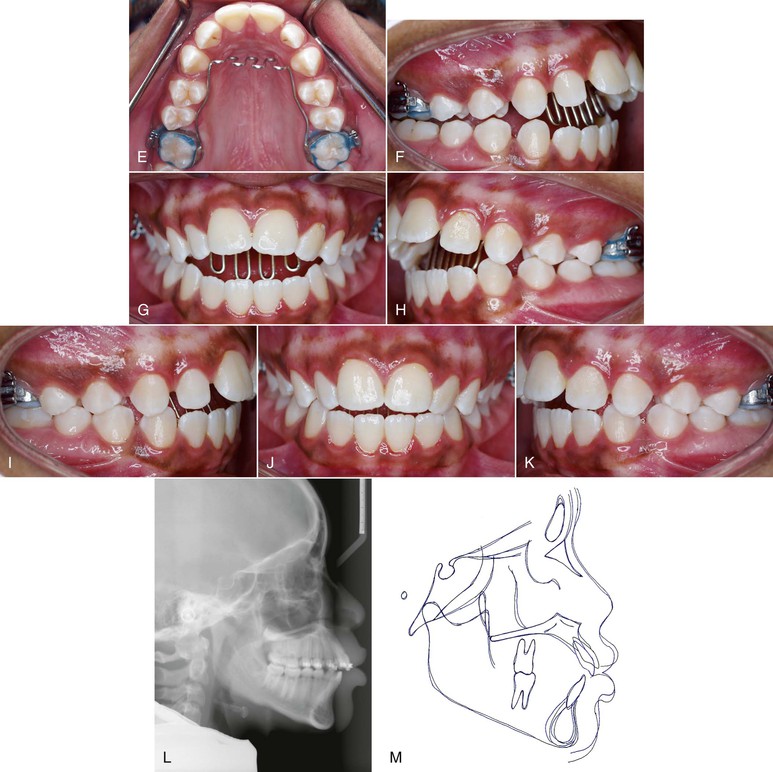

Figure 9-8 A–C, Patient with a finger-sucking habit resulting in an anterior open bite mesial to the first premolars. D, Lateral cephalogram showing characteristics of a dental open bite. E–H, Habit appliance with loops acting as a mechanical obstruction in close approximation to the anterior portion of the palate. I–K, Spontaneous correction of the anterior open bite after habit appliance delivery. L, Lateral cephalogram showing the open-bite closure. M, Superimposition reflecting the incisor extrusion that results with spontaneous closure of an anterior open bite with the habit appliance.

Patients with tongue thrusting can be treated effectively in the same manner as that used for patients who suck on a thumb or finger (Fig. 9-9), although different appliances, such as the habit appliance with lingual spurs or cribs (Fig. 9-10), have been suggested. In one study,62 immediately after crib placement the tip of the tongue was positioned posteriorly during all stages of deglutition. Additionally, the anterior and middle parts of the dorsum of the tongue were at a lower position, reflecting a compensatory functional change for bolus propulsion and airway protection. However, no significant change occurred in the posterior part of the dorsum. Taslan et al.63 reported a decrease in resting tongue pressure and swallowing pressure from 21 g/cm2 to 13 g/cm2 and 216 g/cm2 to 143 g/cm2, respectively, after 10 months of tongue crib therapy in patients with anterior open bite. This decrease in tongue pressure at rest and swallowing pressure after crib therapy was suggestive of tongue adaptation in response to the altered environmental changes. This altered tongue posture aided in the correction of an anterior open bite through an increase in overbite of 3.6-mm. The increase in overbite was attained by lingual inclination of the maxillary and mandibular incisors by 4 degrees each and by extrusion of 1.4-mm and 1-mm, respectively.64